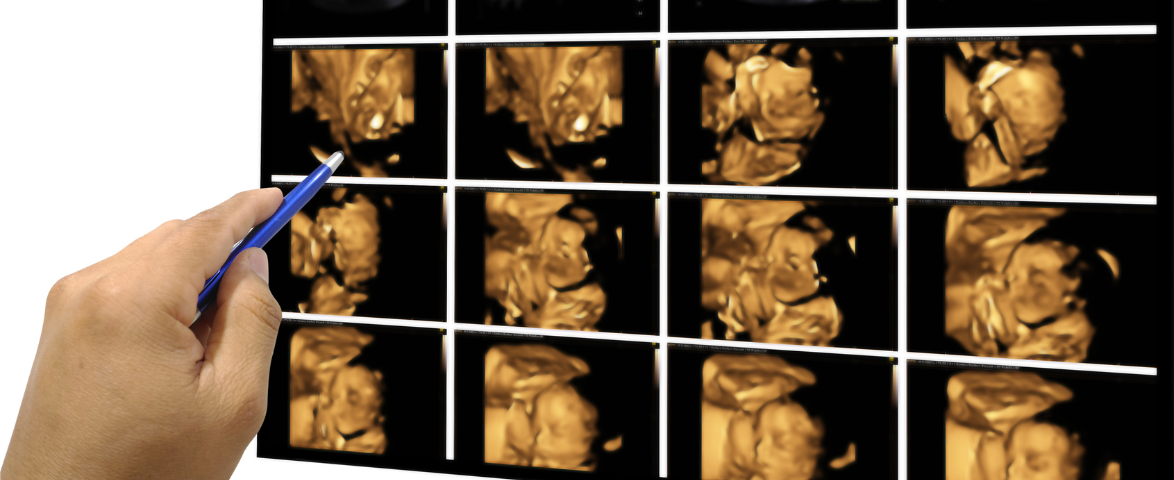

3D Ultrasound  – See Your Baby in Clear Detail

A 3D ultrasound  is a medical imaging procedure that uses high-frequency sound waves and advanced software to produce clear, sharp images of your baby’s tissues, organs, and other body parts. Unlike standard ultrasounds, 3D imaging provides lifelike pictures of the fetus, allowing parents to bond while helping doctors monitor fetal health.

The 3D ultrasound procedure is simple and non-invasive. A gel is applied to the mother’s belly, and a probe is gently moved over the abdomen. The probe sends sound waves toward the uterus and fetus, creating detailed images. This safe procedure provides accurate 3D sonogram diagnosis, helping doctors assess fetal development effectively.

A pregnant woman can undergo a 3D ultrasound at any stage of pregnancy. However, the best time for this scan is after 20+ weeks of gestation, when the fetus has developed enough for clear imaging. This timing ensures the most detailed and accurate views of your baby’s features and movements.